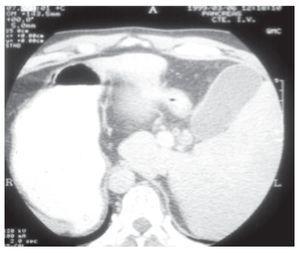

A la exploración física, se encontró con tensión arterial de 130/80 mmHg, frecuencia cardiaca de 85 latidos por minuto, frecuencia respiratoria 18 por min, temperatura de 37.8 ºC. Se apreciaba deshidratación de mucosas, ictericia de piel y escleras, así como estertores en la base pulmonar derecha. El abdomen era blando y depresible, doloroso en epigastrio y cuadrante superior izquierdo, con peristalsis presente. No se palparon masas. El resto del examen físico fue normal. Los exámenes de laboratorio mostraron hemoglobina de 18.2 g/dL, hematócrito de 53%, leucocitos: 7.3 mil células/ mm3, glucosa: 121 mg/dL, BUN: 9 mg/dL, creatinina: 1.0 mg/dL, bilirrubina total de 5.8 mg/dL, bilirrubina directa: 4.4 mg/dL e indirecta: 1.38 mg/ dL, fosfatasa alcalina: 174 UI/L, aspartato amino-transferasa: 151 UI/L y alanina aminotransferasa: 259 UI/L. El ultrasonido abdominal informó hígado situado en cuadrante superior izquierdo del abdomen, con vesícula biliar distendida, pared de 4.5 mm de espesor, con ecos en su interior sugestivos de lodo biliar y el colédoco medía 7 mm. La tomografía computarizada abdominal confirmó el situs inversus y edema importante de la pared vesicular (Figura 1). Se inició hidratación intravenosa y ciprofloxacino. Se comentaron las diferentes alternativas de tratamiento con el paciente y se decidió su intervención quirúrgica por vía laparoscópica para resolver el cuadro de colecistitis aguda y la ictericia obstructiva.

¿ Figura 1. TC de abdomen mostrando el situs inversus y la pared vesicular con edema.